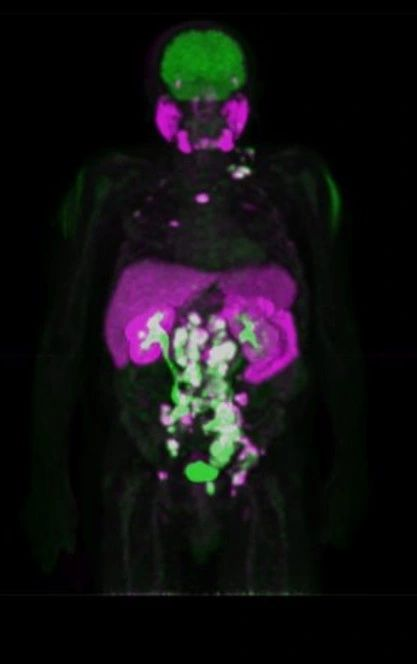

Συνδυάζουμε στοχευμένα ραδιοφάρμακα που απεικονίζουν και θεραπεύουν τον ίδιο μοριακό στόχο. Στο ΥΓΕΙΑ το πρόγραμμα αφορά:

PSMA‑θετικός καρκίνος προστάτη

Νευροενδοκρινικοί όγκοι (SSTR)